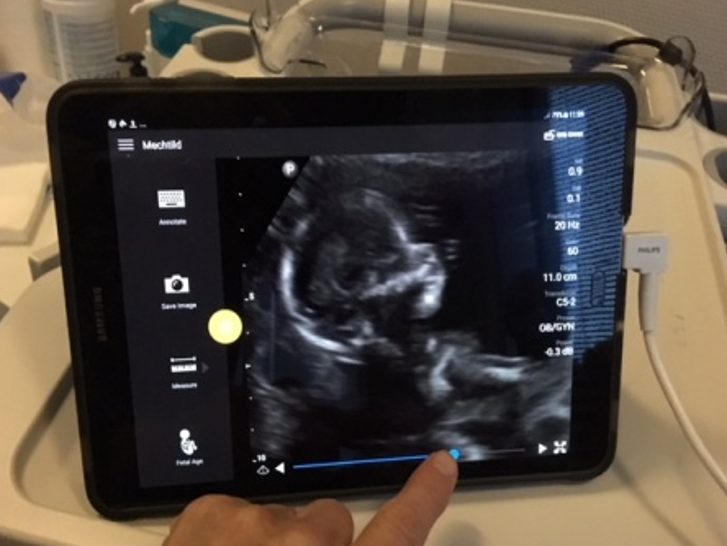

Twee studenten op echostage in Zanzibar

Twee van onze studenten die recent de echo-opleiding in Dodoma hebben afgerond, Yohana en Noela, zijn aansluitend naar Zanzibar afgereisd voor een aanvullende echostage van twee weken bij onze lokale...